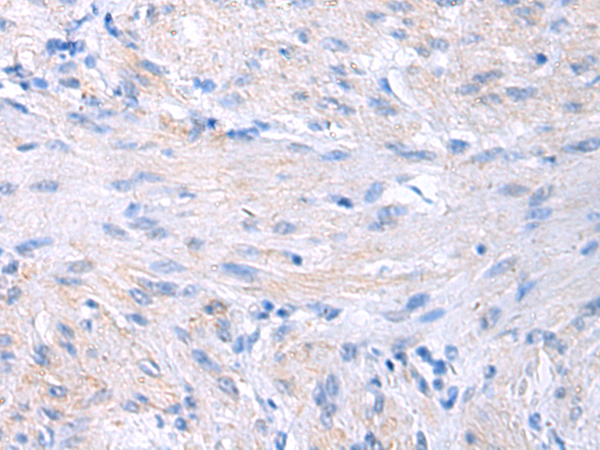

分类: 科研抗体货号: P06470别名: EVI1; MDS1; KMT8E; PRDM3; RUSAT2; MDS1-EVI1; AML1-EVI-1应用: WB,IHC反应种属: Human, Mouse